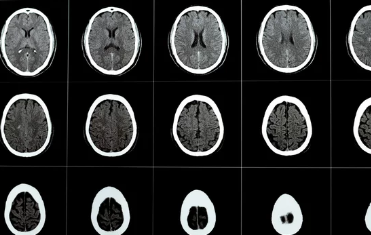

3. 뇌혈전증 진단: 병력 청취, 신경학적 검사, 영상 검사

뇌혈전증 진단은 다음과 같은 과정을 통해 이루어집니다.

- 병력 청취: 환자의 증상, 과거 병력, 가족력, 복용 중인 약물 등에 대해 자세히 질문하여 뇌혈전증을 의심합니다.

- 신경학적 검사: 의식 수준, 운동 기능, 감각 기능, 언어 기능, 시야 등을 평가하여 뇌 손상 부위와 정도를 파악합니다.

- 영상 검사: 뇌 CT, MRI, MRA 등 영상 검사를 통해 뇌혈관 막힘 여부와 위치, 뇌 손상 정도를 확인합니다.